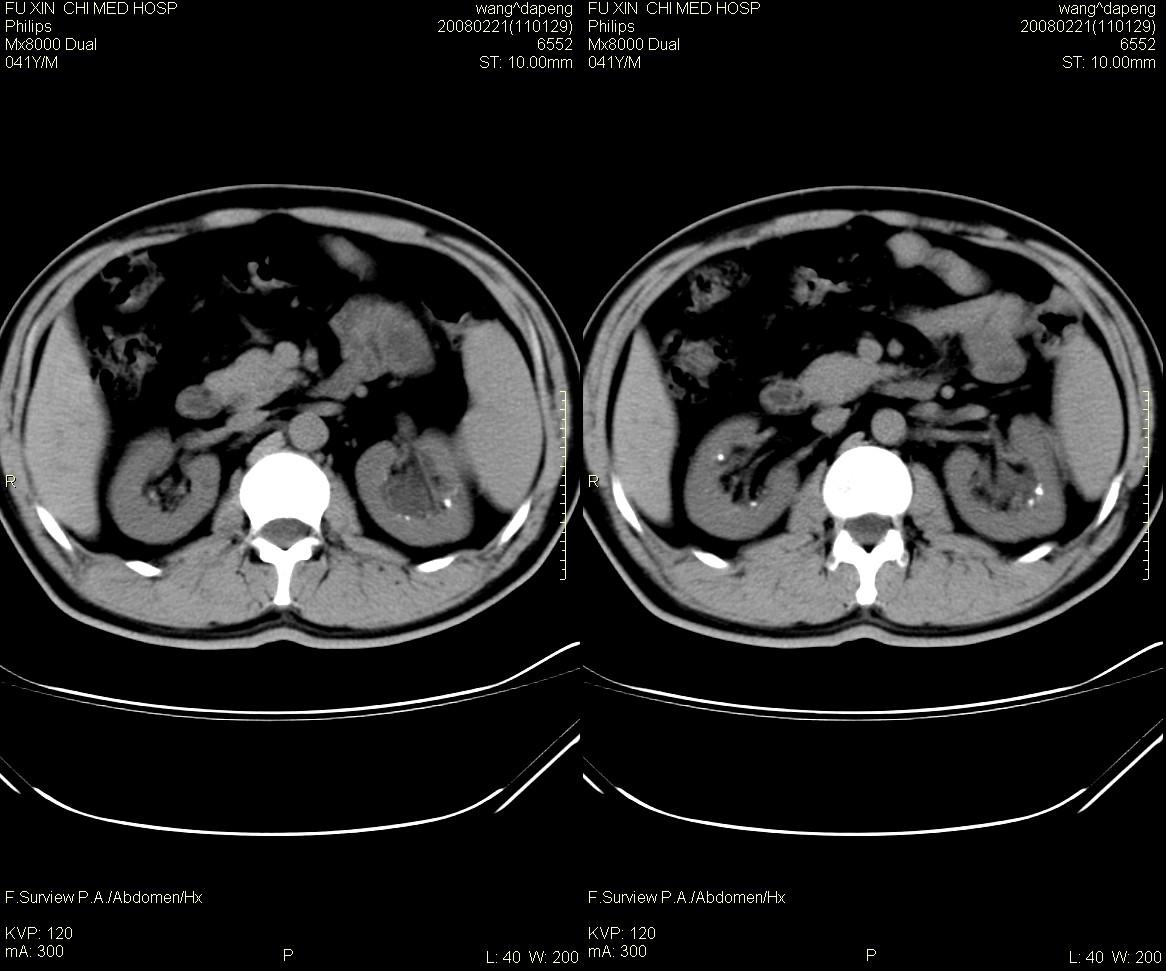

髓质海绵肾是一种先天性的肾髓质囊性病变, 其特征为肾锥体部乳头管及集合管呈梭形或囊状扩张,并伴发感染和尿路结石形成。在肾标本切面上, 可见髓质中呈海绵状改变。ct平扫表现为肾盏旁锥体内多发小斑点状结石, 成扇形排列.增强扫描后扩张的肾集合管内结石周围有造影剂充盈, 无结石的肾锥体集合管呈条纹状或小囊状造影剂积聚,肾功能正常.

海绵肾是先天性的,可能是有遗传倾向的良性肾髓质囊性病变,常于40岁以后发现,易误诊断肾结石和尿路感染。其病理特征是肾小管远端集合小管扩张,形成小囊和囊性空腔,并位于肾盏连接处,易导致结石、感染等。病变一般为双侧性80%的病人部分或全部肾乳头受累。临床上病变局限,轻微者可无明显症状,常见的症状为腰痛、血尿、尿路感染及肾绞痛等。

海绵肾的影像诊断主要靠静脉尿路造影,在平片上表现为双侧肾盏处侧有多发的小结石影。造影后显示肾乳头囊状扩张,内见单发或多发的钙化点,表现为环绕于肾盏、肾盂周围的多数囊腔,形似菜花。ct对海绵肾集合小管囊状扩张的空间分辨率不如ivu高,但对检出其中的小结石较x线敏感。因此,可疑海绵肾的影像诊断应结合上述两种检查。

鉴别诊断:1)肾结石:位于肾盂或肾小盏内,增强后排泌的造影剂常把结石掩盖,较大的结石常使其以远的肾盏发生梗阻性积水。2)肾结核:一般常单侧发生,肾实质内可见单发或多发大小不等、形态不一的囊腔,囊壁有钙化斑,局部肾盏可见不规则的破坏或造影剂充盈不佳,常并发有肾盏、肾盂积水。3)肾乳头坏死:愈合期表现为集合小管内或周围弥散性钙盐沉积,钙化较海绵肾更广泛。